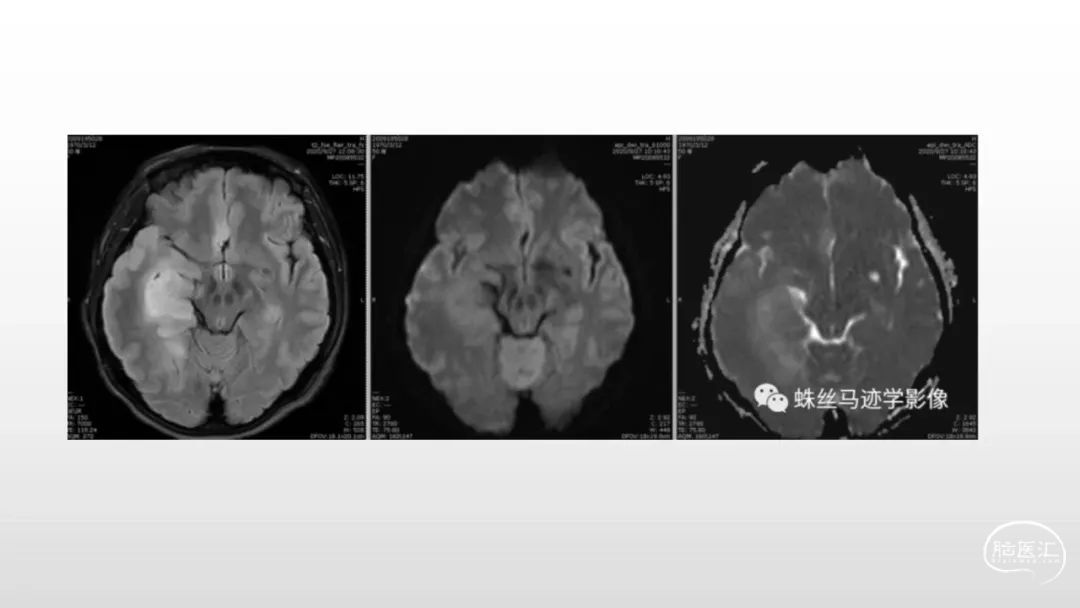

颅脑影像诊断基础知识讲座:感染和免疫性疾病2